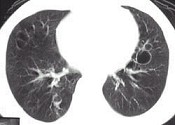

- 单项选择题女,23岁, 咳嗽咳痰反复发作,根据CT图像, 应考虑为 ( )

A、支气管扩张并感染

B、多发肺气囊肿

C、多发性肺囊肿并感染

D、多发性肺脓肿

E、大叶性肺炎